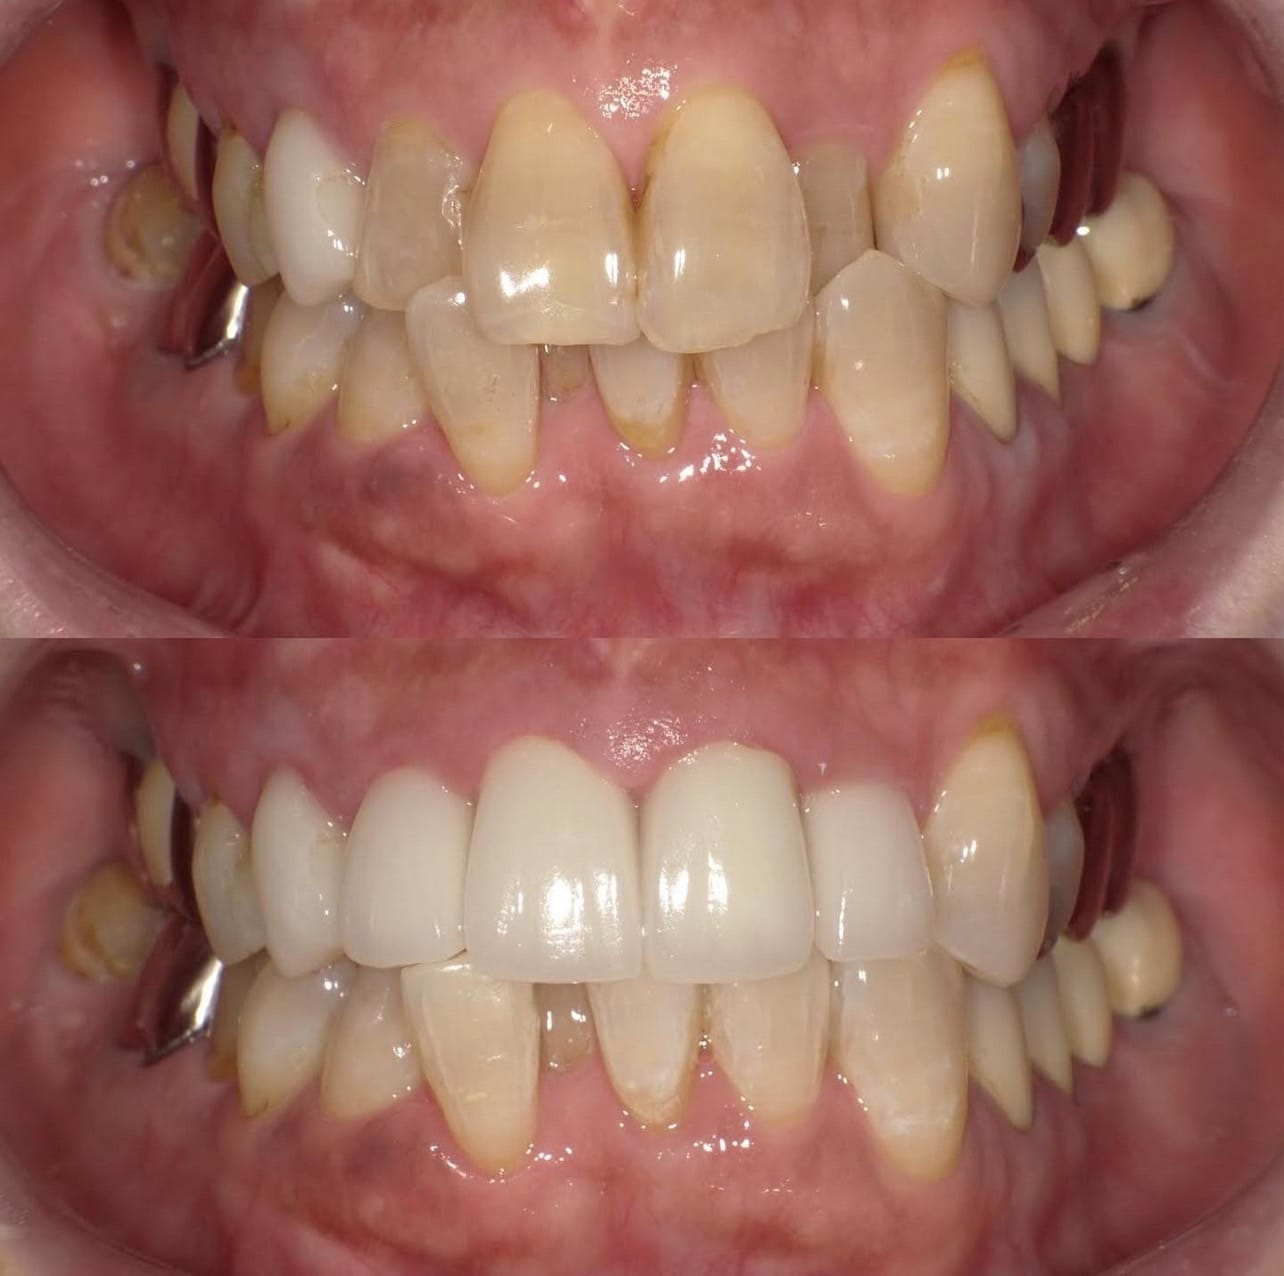

「ずっと放置してしまっていた。今回はちゃんとしっかり治したい」ということで、強い意志をもって来院してくださった患者様の症例です。

インプラント治療、セラミック治療、歯周病治療により、審美性と機能、咬みあわせの再建を行いました。

患者様は咬みあわせの確立により、食事もしやすく、普段の顎関節の状況も良くなり、機能の回復にも満足してくださり、また審美性も喜んでくださいました。

放置期間が長くだいぶ骨が溶けてしまっていたので、前歯部のインプラントは骨の再生療法などが必要だったりしましたが、患者様が治療への前向きな姿勢をだしてくださっていましたので期間も最短で終わりました。

一度放置してしまうと、億劫になってしまってなかなか行動に移すのは難しいと思いますが、少しでも早く治してあげた方が毎日の食事も楽になりますし、お顔の見栄えもお顔の骨格の歪みも改善します。